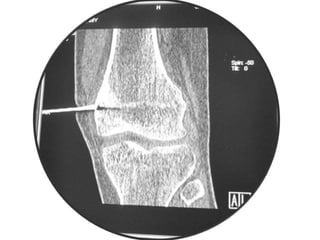

Osteoid Osteoma - Tx

• Excision of the osteoid osteoma nidus using

CT–assisted localization, a Kirschner wire

inserted into the nidus, and a biopsy punch

inserted over the Kirschner wire into the

bone.

• They recommend using a trephine 2 mm

larger than the lesion for complete removal.

• A CT guided needle was passed to localize the

lesion.

• Through an anterior "Hernia" approach the

lesion was approached and excised.

• The Follow-up CT Scanning done to reveal

complete removal of lesion.

• A biopsy confirmed it later.

Osteoid Osteoma -Tx • Excision of the osteoid osteoma nidus using CT–assisted localization, a Kirschner wire inserted into the nidus, and a biopsy punch inserted over the Kirschner wire into the bone. • They recommend using a trephine 2 mm larger than the lesion for complete removal. • Recurrence after apparently complete excision has been reported but is rare.

• A CTguided needle was passed to localize the lesion. • Through an anterior "Hernia" approach the lesion was approached and excised. • The Follow-up CT Scanning done to reveal complete removal of lesion. • A biopsy confirmed it later.